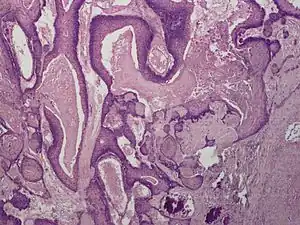

Proliferating trichilemmal cysts (also known as a "Pilar tumor", "Proliferating follicular cystic neoplasm", "Proliferating pilar tumor", and "Proliferating trichilemmal tumor"[2]) are a cutaneous condition characterized by proliferations of squamous cells forming scroll-like structures.[2][3]: 678

pathology-Proliferating trichilemmal cyst -